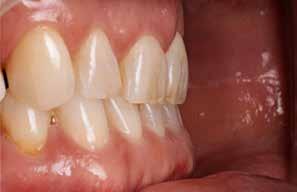

Den kliniske undersøgelse viser harmoniske ekstraorale sagittale forhold med skeletalt dybt bid (Fig. 1A, D). Hendes smil er alderssvarende med en eksponering på 8/10 af overkæbeincisiverne, mens smilets bredde er smalt med synlige mørke laterale rum (Fig. 1D). Underkæbeincisiverne er synlige under tale. Der ses neutrale okklusale forhold ved hjørnetænderne og neutrale pladsforhold i overkæben, men udtalt trangstilling i underkæben især lokaliseret i regio 1-1 (Fig. 1C).

Sliddet klassificeres som grad 2 (moderat tandslid) på de centrale incisiver i overkæbe og underkæbe. Det kan anses som patologisk, da det er atypisk for patientens alder, giver anledning til smerte/ubehag, og giver patienten et æstetisk problem. Der ses infraktioner af overkæbeincisiverne. Der ses endvidere en udtalt Spee-kurve i underkæben og ingen interincisal afstøtning på 2-2 med let ganepåbidning.

Røntgenanalyse viser fravær af -6 samt et velholdt tandsæt uden tegn på sygdom. Profilrøntgenbilledet viser et skeletalt

dybt bid, men normal inklination af fortænder i over- og underkæbe (Fig. 1B).